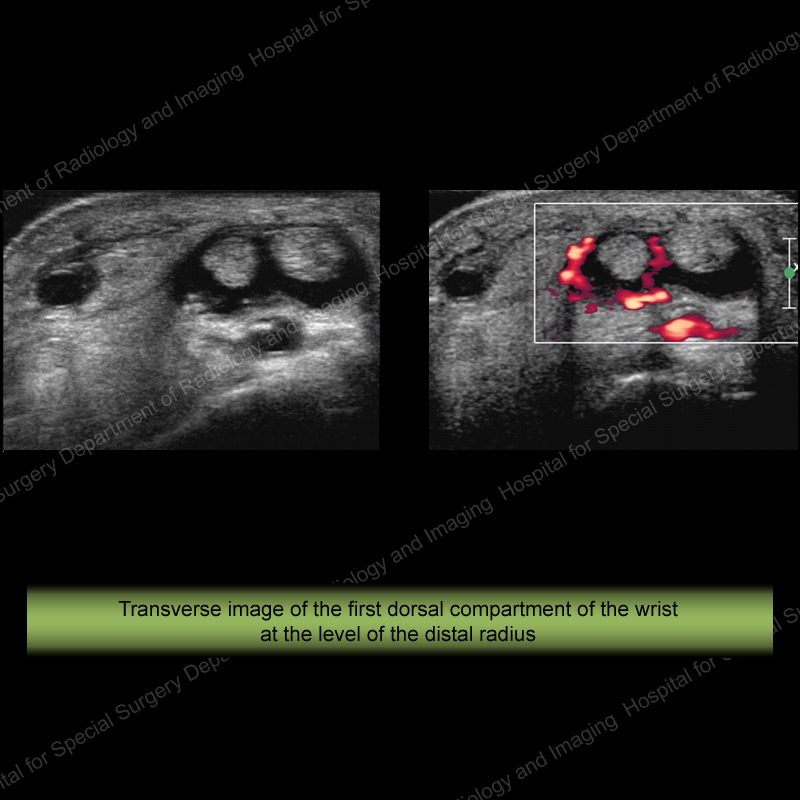

History: 75-year-old male complaining of wrist pain radiating up the forearm

Below: Cine loop showing marked peritendinous hyperemia

Diagnosis: De Quervain’s tendinitis/tenosynovitis Large tendon sheath effusion, inhomogeneity of the first dorsal compartment tendons with marked hyperemia on power Doppler imaging.